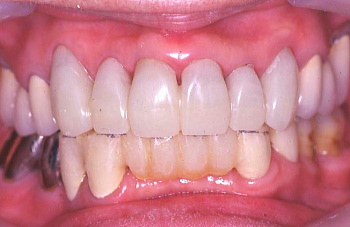

① 初診時の口腔内の状態:歯と歯の間に黒い歯石が見られ、歯肉は腫れている。

② 患者の熱心な歯磨きと医師や衛生士の機械的な歯のクリーニング(PMTC)により、 歯肉は艶を取り戻した。